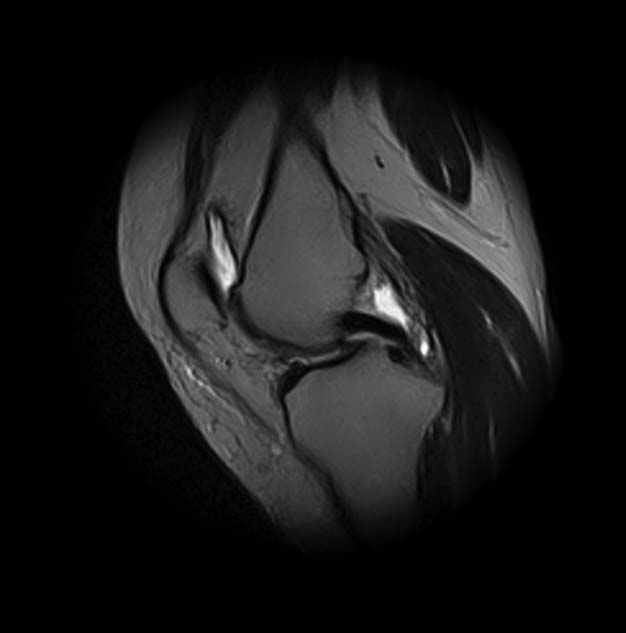

[Ortho] Показания для артроскопии

1. травма 5 лет назад - "ударилась коленом", с тех пор боли в суставе

3. стандартные рентгенограммы с небольшими изменениями - сужение

медиальной суставной щели

4. вес пациентки 80 кг, рост 165

5. сустав клинически стабилен